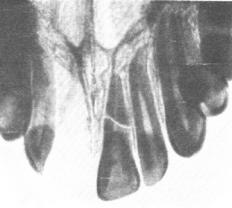

Перелом корня, локализация, смещение отломков, состояние периодонта и альвеолярных отростков устанавливаются при рентгенологическом исследовании. Однако рентгенограммы, сделанные непосредственно после травмы, не всегда позволяют поставить диагноз перелома корня из-за плотного прилегания отломков. Поэтому при подозрении на перелом рекомендуется повторить рентгенографию через неделю. К этому времени формируется кровяной сгусток между отломками и линия перелома на снимке определяется более четко.

Рис. 19: Косой перелом корня зуба